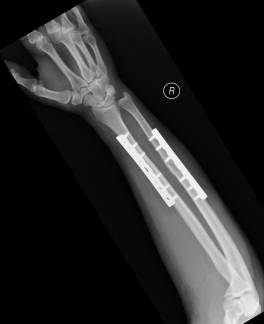

Giriraj orthopedic trauma surgeons offer treatment for these unplanned, critical events - major and minor fractures, nerve and tendon injuries, joint dislocation and other orthopedic injuries. Our surgeons provide expert, compassionate care for patients and their families in these emergencies, beginning with new, less invasive techniques for highly specialized reconstructive surgeries. As a Level One Trauma Center, Giriraj Hospital provides the highest level of emergency care in with state-of-the-art facilities and services. Our orthopedic surgeons are fellowship-trained and experts in orthopedic surgery, so our patients receive highly specialized emergency and follow-up care.

Additionally, Giriraj Hospital's high-tech imaging and surgical equipment can give patients and families choices in their treatment or therapy. For example, depending on the injury, patients may have surgical, medicinal or therapeutic options - or a combination of all three types of therapy. Our experienced Giriraj Hospital trauma team to provide comprehensive care to acutely injured patients. This multidisciplinary team includes general surgery trauma surgeons, nursing staff, mid-level providers and therapists.